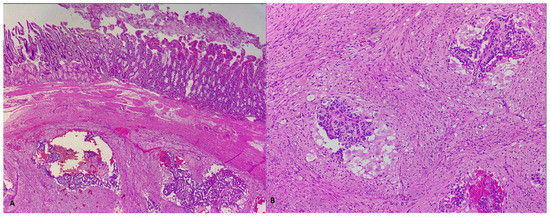

3. Case Report 2